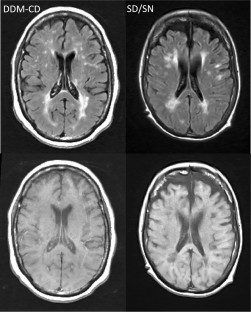

A subgroup of people with multiple sclerosis (pwMS) will develop severe disability. The pathophysiology underlying severe MS is unknown. The comprehensive assessment of severely affected MS (CASA–MS) was a case-controlled study that compared severely disabled in skilled nursing (SD/SN) (EDSS ≥ 7.0) to less-disabled (EDSS 3.0–6.5) community dwelling (CD) progressive pwMS, matched on age-, sex- and disease-duration (DDM).

42 SD/SN and 42 DDM–CD were enrolled. SD/SN pwMS showed significantly lower cortical volume (CV) (p < 0.001, d = 1.375) and thalamic volume (p < 0.001, d = 0.972) compared to DDM–CD pwMS. In a logistic stepwise regression model, the SD/SN pwMS were best differentiated from the DDM–CD pwMS by lower CV (p < 0.001) as the only significant predictor, with the accuracy of 82.3%. No significant differences between the two groups were observed for medulla oblongata volume, a proxy for spinal cord atrophy and white matter lesion burden, while there was a statistical trend for numerically higher sGFAP in SD/SN pwMS.

The CASA–MS study showed significantly more gray matter atrophy in severe compared to less-severe progressive MS.